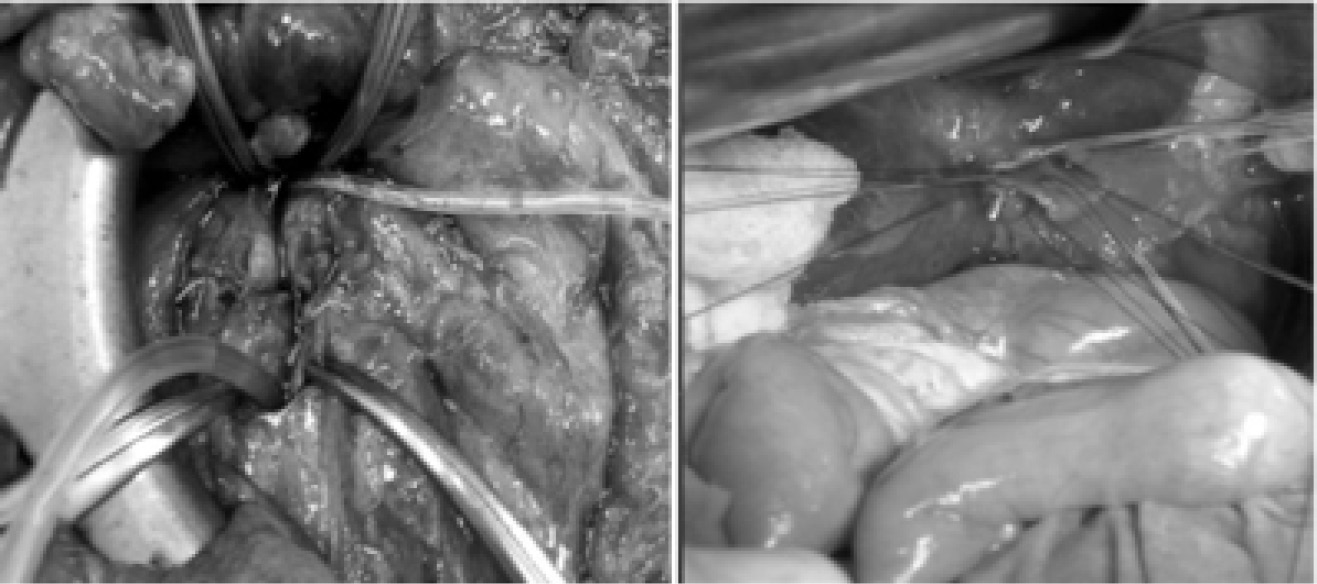

По нашему мнению, важнейшим элементом профилактики осложнений со стороны культи ПЖ и обеспечения благоприятных условий для заживления панкреатокишечного анастомоза, его герметичности является адекватная декомпрессия протоковой системы культи железы в раннем послеоперационном периоде. На восстановительном этапе ГПДР анастомозы формировали последовательно на одной петле тощей кишки, которую провели через окно в брыжейке поперечной ободочной кишки. Первым формировали панкреатокишечное соустье, которое было проксимальным, затем последовательно выполняли билиодигестивный и желудочно-кишечный анастомозы.

Декомпрессию панкреато- и билиодигестивного анастомозов производили с помощью длительного каркасного дренирования ГПП (рис. 5).

Рис. 5. Этапы наложения панкреато- и холедохоэнтероанастомозов. А) Панкреатоэнтероанастомоз. Б) Холедохоэнтероанастомоз